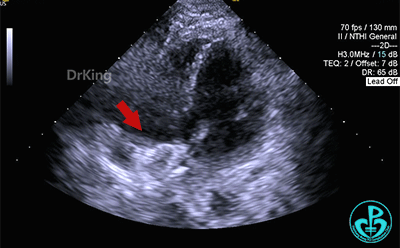

释放封堵器

主动脉短轴切面下观察,封堵器位置正确呈Y字形抱住主动脉根部,形态良好,未见残余分流。

剑下双房心切面显示封堵器呈夹持稳定。

完全释放后超声观察封堵器形态良好,未见分流,封堵成功。